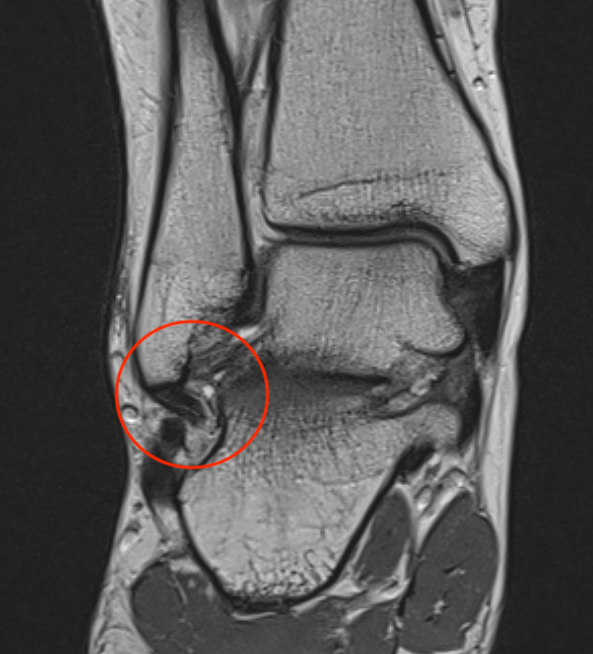

MRI

ATFL tear

CFL tear